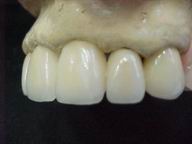

Reabilitação funcional e estética em ambas as arcadas

com próteses fixas e removíveis de encaixe de precisão.

Vista Lateral Esquerda